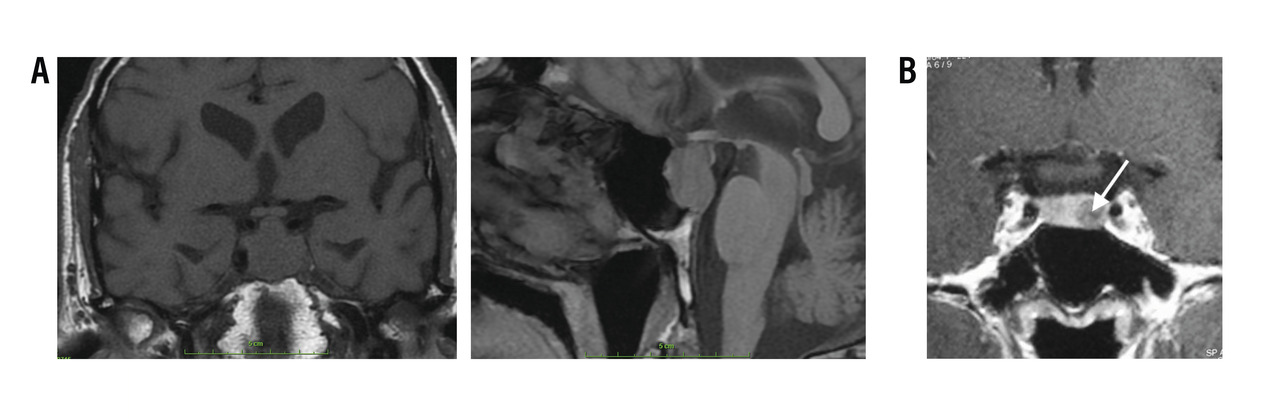

L’imagerie de référence est l’IRM hypophysaire, en coupe fine, avec injection (rang B).

Les micro-adénomes (< 10 mm) sont intrasellaires, ils apparaissent arrondis, homogènes (rang B), en hypo­signal en T1 et hypo-, iso- ou hypersignal en T2 (rang C). La prise de contraste est homogène, volontiers retardée par rapport au parenchyme sain (fig. 5) [rang C].

Les macro-adénomes (> 10 mm) s’étendent en extrasellaire (rang B), leur signal est iso-T1, et souvent hétérogène en T2, les plages nécrotiques apparaissent en hypersignal T2 (rang C). La prise de contraste est le plus souvent hétéro­gène hypo-intense par rapport à l’hypophyse saine (fig. 5) [rang C].